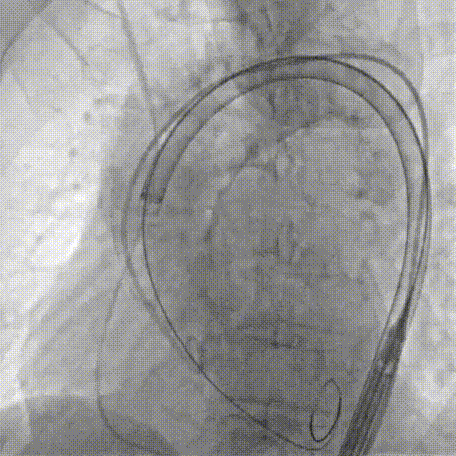

Step 1.升主动脉情况评估

Step 2.建立大鞘通路:大鞘通过升主、边进入边加弯,避免剐蹭弓部斑块